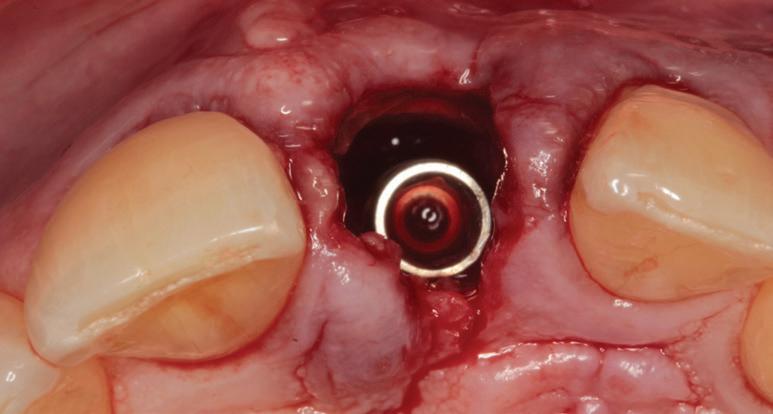

RECONSTITUIREA țesuturilor moi periimplantare. Scopul acestui raport de caz este de a demonstra procedurile chirurgicale utilizate pentru corectarea unui defect al țesuturilor moi periimplantare folosind țesutul moale interdentar în combinație cu tuberozitatea ca locație donatoare de țesut conjunctiv, utilizând o abordare prin tunelizare într-o zonă estetică.

Utilizarea platform-switch și-a dovedit eficiența în sistemele moderne de implanturi. Însă acum, zona conică inversată oferă mai mult spațiu și un suport mai bun de aderență pentru țesutul dur și moale decât formele cilindrice ale implanturilor, așa cum cum se poate vedea în imaginea următoare.

Suprafața microstructurată din zona conică inversată sprijină atașarea osului și a țesutului conjunctiv. Atunci când marginea acesteia este poziționată subcrestal, este recomandată utilizarea unui material de augmentare (xenogrefă sau os autolog) care poate preveni dezvoltarea țesutului moale în zona conică inversată și poate oferi suport pentru o mai bună osteointegrare.

Datorită designului șurubului de acoperire, care are un diametru mic și formă concavă, nu se irită țesuturile periimplantare în momentul în care se intervine în vederea montării formatorului gingival. Osul nou format pe șurubul de acoperire anodizat poate fi îndepărtat cu ușurință cu ajutorul unei chiurete.